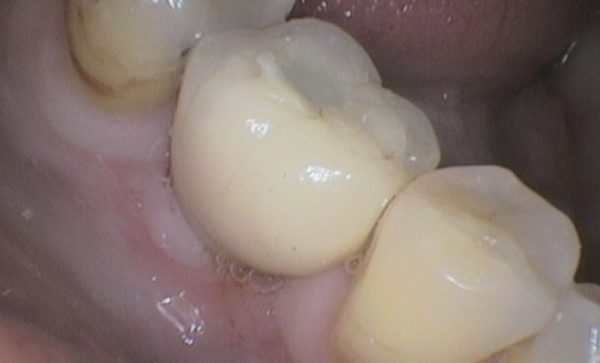

I have been a patient of Dr Verma for 8 years, my treatment has included crowns and an implant. Treatment plans and options are explained to me clearly, my concerns and anxieties are allieviated without hurry or pressure in a gentle and reassuring way. I feel my patient satisfaction is valued.

Sukal has been my dentist for many years, from simple check ups to a dental implant! I have always felt comfortable in the dentist chair and happily watched the TV on the ceiling while work is done on my teeth and never once felt any pain and always felt comfortable. I would never go anywhere else! Thank you all for being kind, caring and helpful at all times :-) Sarah Galloway